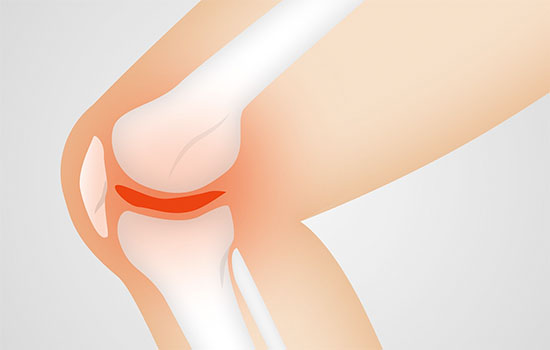

La artrosis se produce cuando el cartílago que rodea la articulación, tejido que amortigua las cargas a las que es sometida la articulación, empieza a deteriorarse. Casi todas las articulaciones pueden verse afectadas en la artrosis, pero las más frecuentes son la rodilla, cadera y pequeñas articulaciones de las manos.